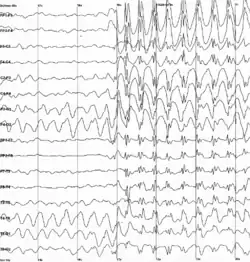

Elektrofyziologická vyšetření v neurologii jsou poměrně specifická pro neurologii. Patří sem zejména EEG, EMG, polysomnografie a evokované potenciály.

Elektroencefalografie (EEG)

Elektroencefalografie je metoda sloužící k měření povrchových potenciálů odpovídajícím sumační aktivitě zejména korových neuronů v poměrně velkých okrscích. EEG má diagnosticky význam především v případě diagnostiky epilepsií, ovšem řada dalších poruch struktury i funkce mozku může mít na záznamu z EEG svůj korelát.